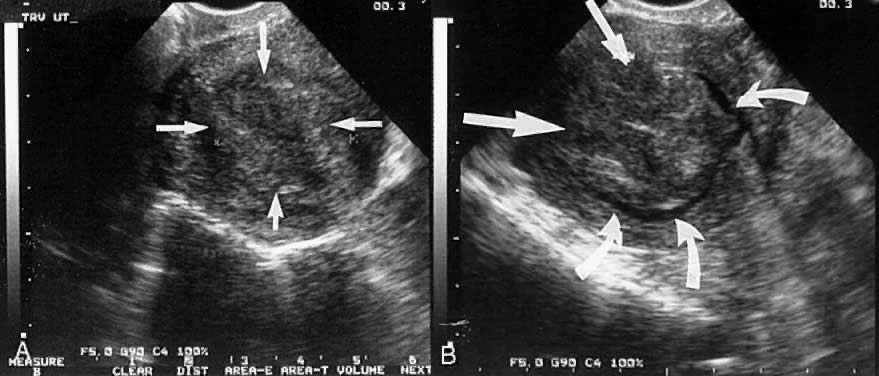

It appears that sonohysterograms are not more sensitive for the detection of submucous leiomyomas than transvaginal scans without infusion. However, this is deceptive, because the degree of myometrial involvement frequently cannot be accurately mapped without saline infusion. This problem can lead to inappropriate case selection (Figs. 8 and 9).

Fig. 8. A. A centrally located leiomyoma is identified (straight arrows). The endometrial stripe is poorly seen. B. After saline infusion (curved arrows), a 3-cm submucous leiomyoma with minimal myometrial extension (category T-I) is identified.

Fig. 9. A. A centrally located leiomyoma is identified, but the endometrial stripe is poorly seen. B. After saline infusion, a submucous leiomyoma with more than 50% penetration into the myometrium (category T-II) is seen.